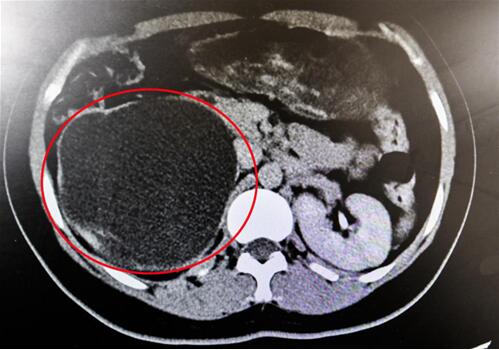

紅圈部分為手術前腎積水情況。院方供圖

“腎臟就像是一個皮球,因輸尿管完全閉鎖,里面的積水無法排出、越積越多,已經把表皮撐得很薄,在造影下甚至都看不清邊緣了!苯纳魅握f,“由于之前手術的粘連嚴重,手術難度頗大,腎臟能否保住是個未知數!